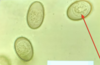

Giardia sp.: Trophozoite

Containing 2 nuclei

Giardia sp.: Trophozoites